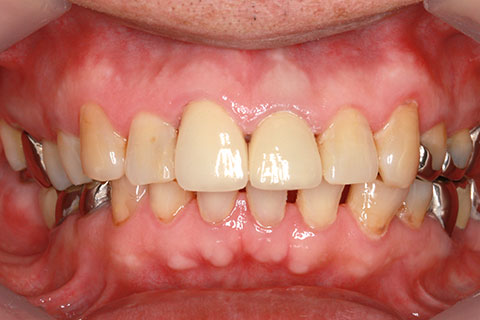

オールセラミックの症例2

- 年齢・性別

- 45歳男性

- 治療期間

- 2ヶ月

- 抜歯

- なし

- 治療費

- 70.4万円

- 備考

- 前歯8本の歯列不正によるセラミック治療

- 治療内容

- 歯質を削除し、セラミック冠をセメント合着

- 施術の副作用(リスク)

- 知覚過敏、歯髄炎、荷重負担